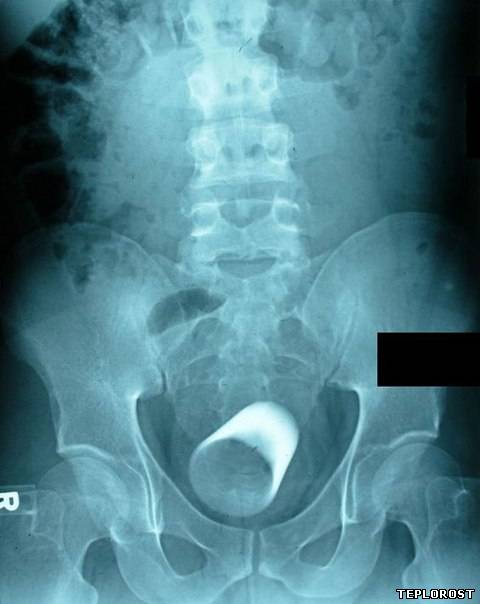

Бильярдный шар во влагалище.